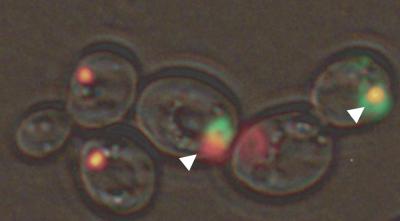

The researchers placed human huntingtin protein with an expanded region, called a polyglutamine tract, into yeast cells and found toxicity differences that were based on the other protein aggregates -- called prions -- present in the cells.

Expanded huntingtin forms clumps in human cells that are typically transported and stored in an internal compartment called an aggresome until they can be removed from the body. While the compartment is thought to protect the contents of the cell from the toxic contents inside the aggresome, the current study shows that huntingtin molecules inside an aggresome can still be toxic to the cell.

In the study, aggresome formation in the cells containing the prion form of the Rnq1 protein reduced the toxicity of the huntingtin protein in Saccharomyces cerevisiae yeast cells, whereas the huntingtin protein's toxicity remained in the presence of the prion form of translation release factor Sup35.